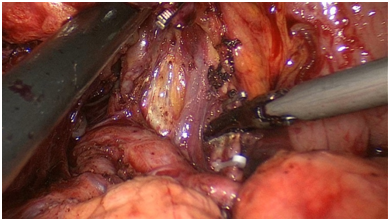

手术图片

腹腔镜直肠癌根治术

腹腔镜胃癌根治术

腹腔镜结肠癌根治术。

腹腔镜胆总管切开取石+T型管引流术

复杂性肝内胆管结石术中胆道镜联合激光碎石术

术中胆道镜取石术

腹腔镜肝脏血管瘤切除术

腹腔镜脾脏部分切除术

腹腔镜腹股沟疝修补术(TAPP)